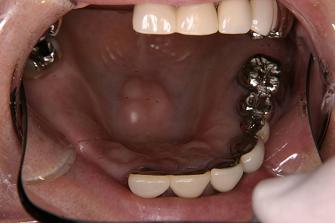

2. 作製したバネなし入れ歯

(バルプラスト)です

裏側